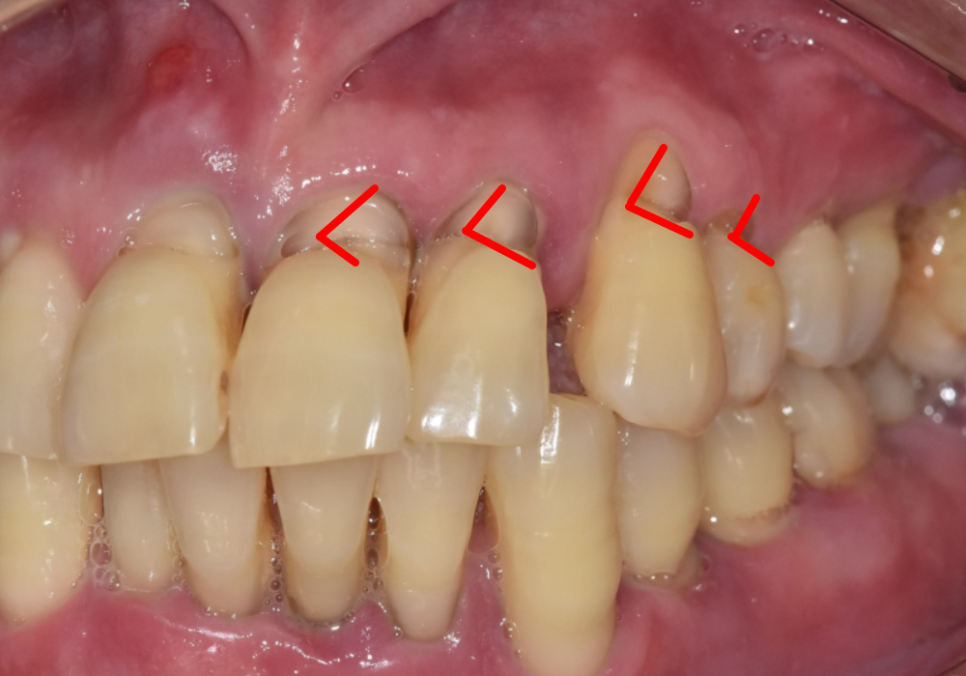

그런데 칫솔을 옆으로 뉘어서 강하게

'좌우로' 닦으면 어떻게 될까요?

마치 거대한 나무를 톱으로 써는 것과

같은 원리가 작용해요.

칫솔모가 치아의 목 부분을 계속해서

강하게 마찰시키면서,

얇은 층이 조금씩 깎여 나가게 됩니다.

잇몸이 미세하게 내려가면서

드러난 약한 부위가 'V'자 형태로

깊게 패어 나가는 것인데,

이를 치경부 마모증이라고 불러요.

얼마 전 저희 치과를 찾으신

고령 환자분의 사례를 소개해 드릴게요.

이 환자분은 치아 뿌리 쪽이

아주 깊게 패어 있는 모습인데요.

오랜 세월 동안 마모가 서서히 진행되어,

육안으로 봐도 치아 안쪽의 신경이

드러날 정도로 심각한 상태였습니다.